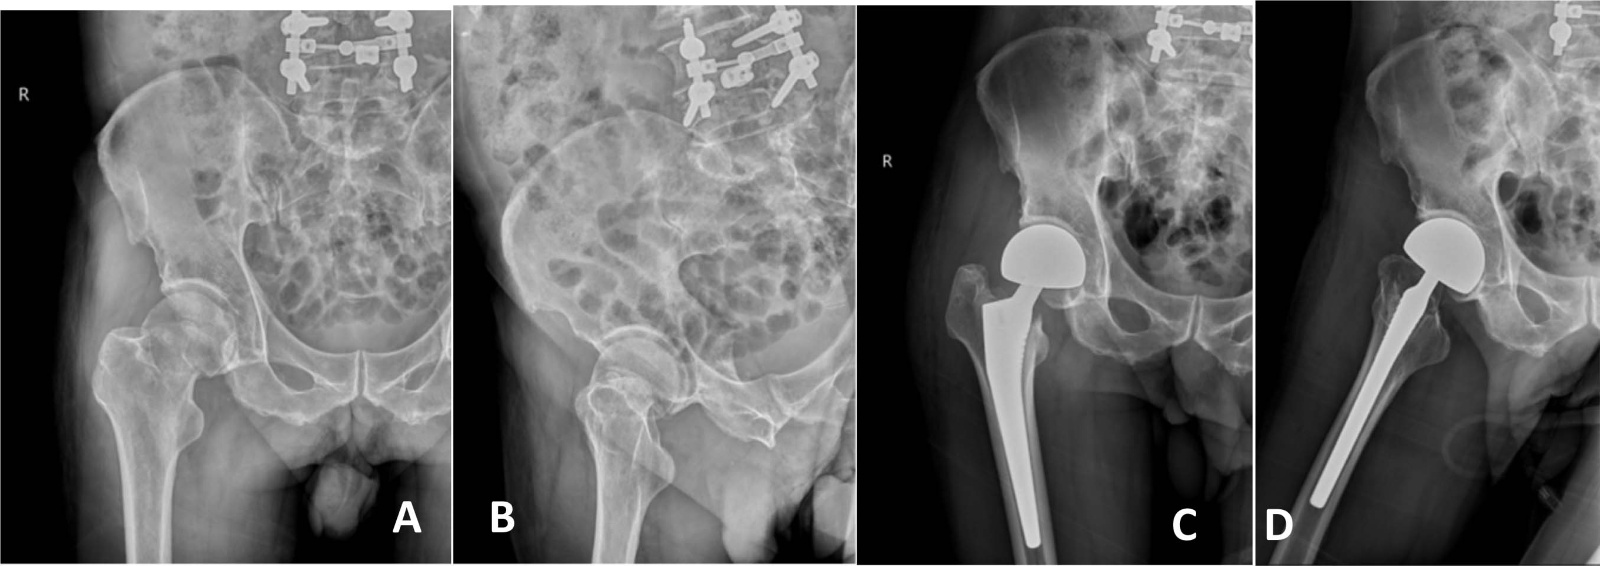

典型病例影像学表现见图1~5图1为76岁女性右侧股骨颈骨折(Garden Ⅲ型)患者,DAA入路半髋关节置换术前X线示骨折断端部分错位,术后X线示假体位置良好,股骨近端微裂予钢丝捆扎固定;图2为83岁女性左侧股骨颈骨折(Garden Ⅳ型)患者,术后X线示假体位置良好;图3为75岁男性右侧股骨颈骨折(Garden Ⅱ型)患者,术后假体位置满意;图4为73岁女性左侧股骨颈骨折(Garden Ⅲ型)患者,术后假体匹配良好;图5为80岁男性右侧股骨颈骨折(Garden Ⅱ型)患者,术后假体位置正常。

Figure 3. X-rays before and after surgery of a 75-year-old male patient with right femoral neck fracture (Garden type II) A, B: Before surgery; C, D: After surgery

3. 75岁男性右侧股骨颈骨折(Garden Ⅱ型)患者手术前后X线片A、B:术前;C、D:术后